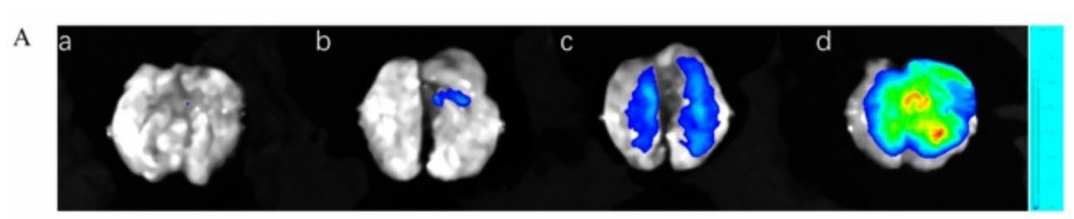

利用Clinx勤翔IVScope 8000系列小动物活体成像系统,以近红外荧光探针 DCIP-ONOO 特异性识别过氧亚硝酸盐(ONOO⁻),在链脲佐菌素(STZ)诱导的糖尿病肝损伤(DLI)小鼠模型中,实现肝损伤动态监测与二甲双胍治疗效果评估。

成像结果:

DLI 模型小鼠肝脏区域荧光信号显著强于正常小鼠,而二甲双胍治疗后荧光信号明显减弱,证实 DCIP-ONOO 可特异性追踪 DLI 进程中 ONOO⁻的变化。探针检测限低至 119.6 nmol/L,生物安全性优异,为糖尿病肝损伤的早期诊断和治疗效果评估提供了无创可视化工具。